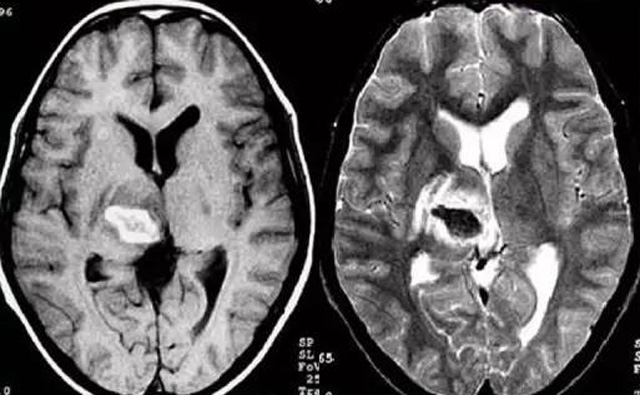

發現病人出血腦梗相關癥狀時候第一時間就醫,需要攜帶以往的影像檢查資料。向醫生提供相關的病史基本資料。做影像檢查時候需要全身不攜帶金屬物品。檢查時候身體保持不動,不然偽影對檢查結果有干擾。磁共振MRI發現缺血性卒中后,幫助進一步查找病因。由于CT上小腦跟腦干顱骨影響,容易導致漏診。MRI檢查可以對CT檢查不足的補充。短暫的腦缺血TIA也需要進行影像檢查。短暫性缺血一般10幾分鐘后好轉。檢查目的可以確定TIA的病因。降低腦梗死的發生率。磁共振有助于排出TIA表現的顱內病變,有診斷及時治療的價值。磁共振MRI檢查時間比較長,不太適合急診病人。但是可以發現腦干小腦的出血問題。因為急性腦梗死的早期和急性期,缺血區的腦組織還沒有完全壞死,頭顱CT不能顯示病灶,所以就需要MRI磁共振檢查,這個對陳舊跟亞急性出血顯示比較好。缺點性價比不高,費用比較貴。頭顱的磁共振MRI在發病后的幾天CT的敏感降低時候發揮大作用。,MRI可作為診斷蛛網膜下腔出血和了解破裂動脈瘤部位的一種重要方法,必要時進一步進行DSA檢查,幫助制訂臨床的手術治療方案,